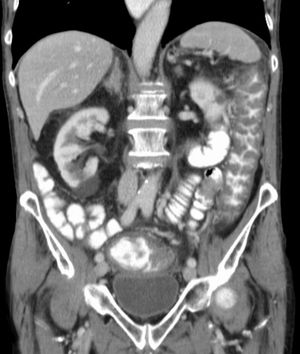

| 합병증 | 가막성 대장염 독성 거대결장 대장 천공 패혈증 |

''C. difficile'' 독소를 검출하는 검사가 나오기 전에는, 결장경 검사나 S상 결장경 검사를 통해 진단하는 경우가 많았다. 결장 또는 직장 점막에서 "가성 막"의 출현은 이 질환을 시사하지만, 진단적인 것은 아니다.[46] 가성 막은 염증성 잔해물과 백혈구로 구성된 삼출물로 이루어져 있다. 현재도 결장경 검사 및 S상 결장경 검사가 사용되기는 하지만, 현재는 ''C. difficile'' 독소 존재 여부를 검사하는 대변 검사가 진단의 첫 번째 단계로 자주 사용된다. 일반적으로 독소 A와 독소 B 두 가지만 검사하지만, 이 균은 다른 독소도 여러 개 생성한다. 이 검사는 100% 정확하지 않으며, 반복 검사에도 위음성률이 상당하다.[47]